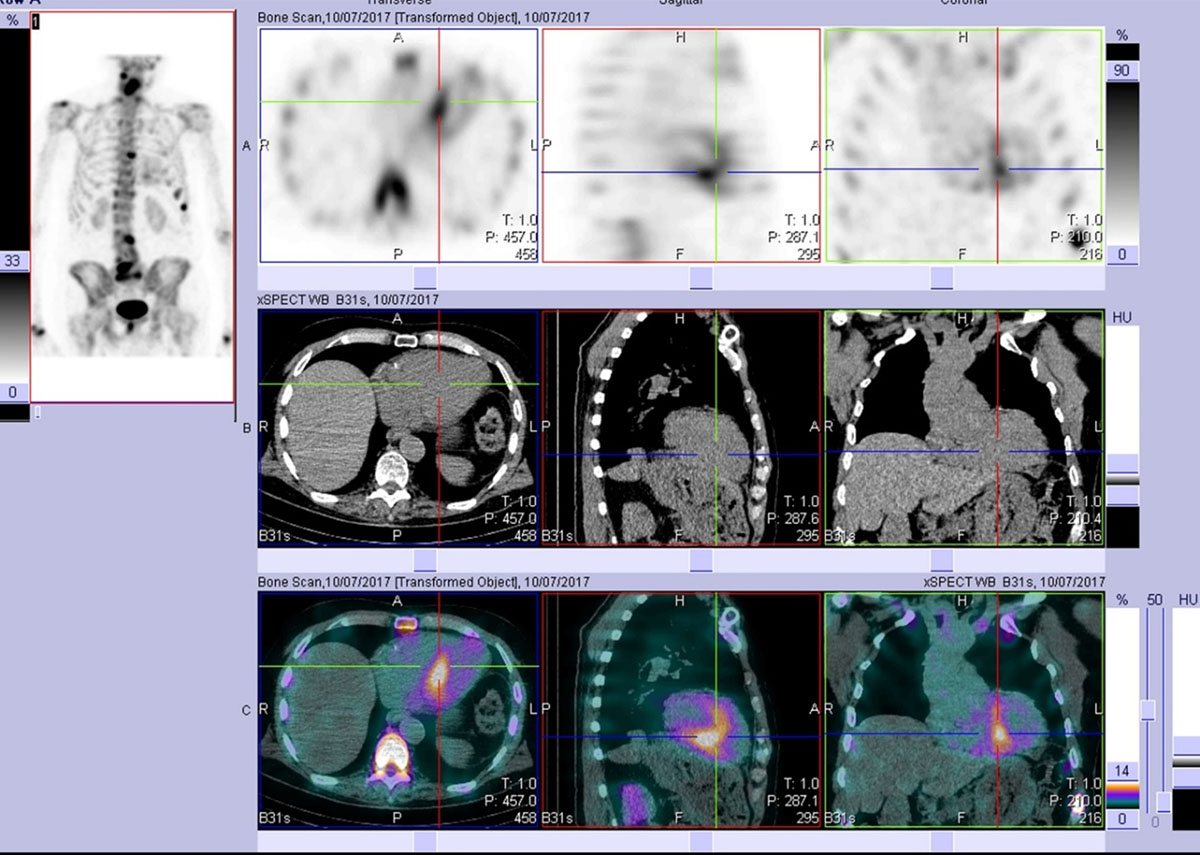

Figure 4

After viewing the planar study, a SPECT-CT was performed. This representative slice in axial, sagittal, and coronal plains (top row = SPECT, middle row = CT, bottom row = merged) confirms the uptake as cardiac and not blood pool. Echocardiogram at the time was normal. The patient developed echo and clinical features of cardiac ATTR amyloid approximately two years later. (Images courtesy of Cabrini Health, Victoria, Australia).